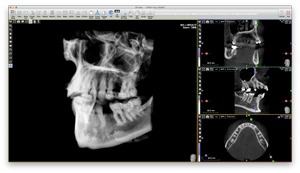

X-Mind® prime сочетает в себе технологии 2D и 3D. Используя один датчик, практикующий врач может быстро и легко переключаться между режимами. Имея 24 панорамных и 32 варианта КЛКТ, X-Mind ® prime охватывает множество клинических применений, включая имплантологию, эндодонтию, визуализацию ВНЧС и пазух, открывая целый ряд новых возможностей.

Несколько FOV для многих приложений (от 50x50 мм до 85x93 мм):

- Полный зубной ряд

- Одна челюсть (верхнечелюстная/нижнечелюстная)

При минимальном размере вокселя 87,5 мкм вы получите подробные трёхмерные реконструкции, способные выделить мельчайшие анатомические элементы.

X-Mind® prime предоставляет множество приложений, предназначенных как для специалистов, так и для врачей общей практики.

- Оценить детальную морфологию костной ткани

- Исследуйте верхнечелюстную пазуху

- Осмотр челюстно-лицевых заболеваний

- Выявление зубных аномалий

- Определить протокол удаления ретенированных зубов

- Диагностика заболеваний височно-нижнечелюстного сустава